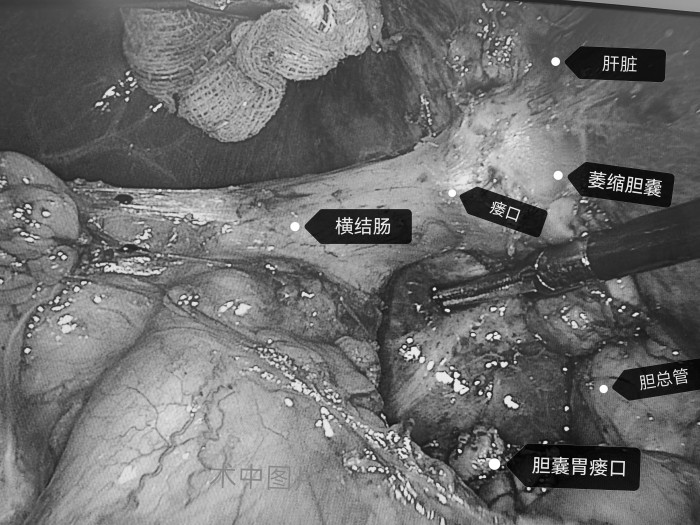

沈紅波為柴女士制定治療方案,行腹腔鏡下膽囊切除術(shù)。術(shù)中見膽囊明顯萎縮,與橫結(jié)腸、胃壁致密粘連,已形成膽囊胃瘺、膽囊結(jié)腸瘺。沈紅波分別修補(bǔ)兩個(gè)瘺口,并切除萎縮的膽囊。